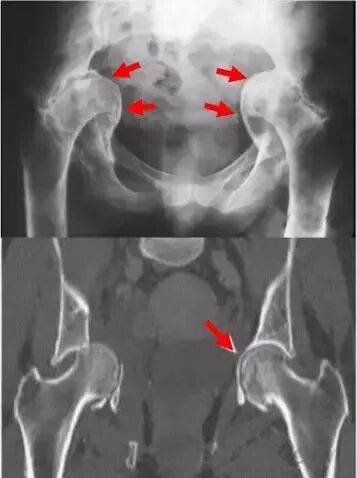

中心边缘角(CE角):

髋臼外上缘到股骨头中心连线与垂线所成之角,正常20°~30°,DDH患者此角变小,反应股骨头旋转中心移位程度,小于20°提示先天性髋臼发育不良。

Sharp角:

在骨盆正位片上,双侧泪滴下缘连线与泪滴下缘至髋臼上缘连线的夹角,正常值为33°~38°,此角大于40°提示髋臼发育不良。

髋臼指数:

成年人则为髋臼外上缘到髋臼窝中心连线与水平线夹角。髋关节结构和发育状况的一个重要判断指标。正常髋臼指数为20°~25°,大于25为髋臼发育不良。

髋日深度:

骨盆正位片,耻骨联合上缘与髋臼外上缘连线至髋臼底的最大距离即为髋臼深度。正常成人:男13(7-18)mm,女12(9-18)mm,临床上常与CE角配合使

用表示骨髋臼发育程度。

髋臼覆盖率:

股骨头受髋臼覆盖部分的横径(A)除以股骨头的横径(B),即为髋臼覆盖率,其正常值应大于075。判断股骨头移位情况。

髂坐线 Kohler line:

从坐骨切迹外侧到闭孔内侧。实际反映髋臼底部(中央部、内壁)的缺损深度及范围。髋臼窝超过髂坐线内侧称为突出。

泪滴组成:外侧有髋臼最下部和前部组成,内侧有髂骨四边形骨面的前部组成。呈U形或泪滴形者表明髋臼窝底部骨质较厚,线条形者骨质菲薄,反应底部壁厚度骨量存留。